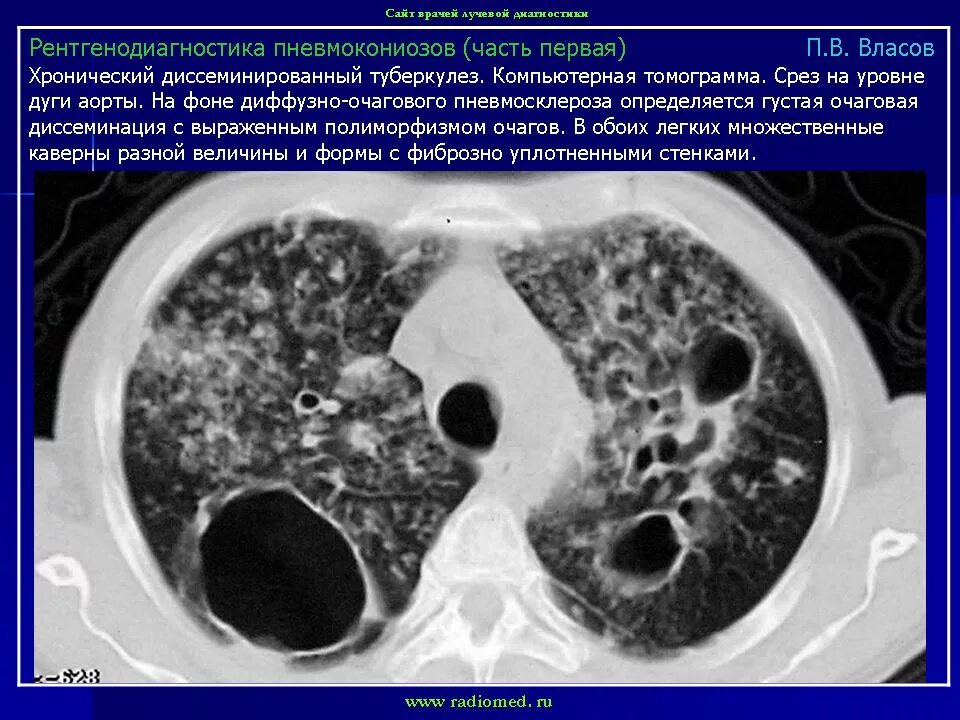

Кт ошибочно